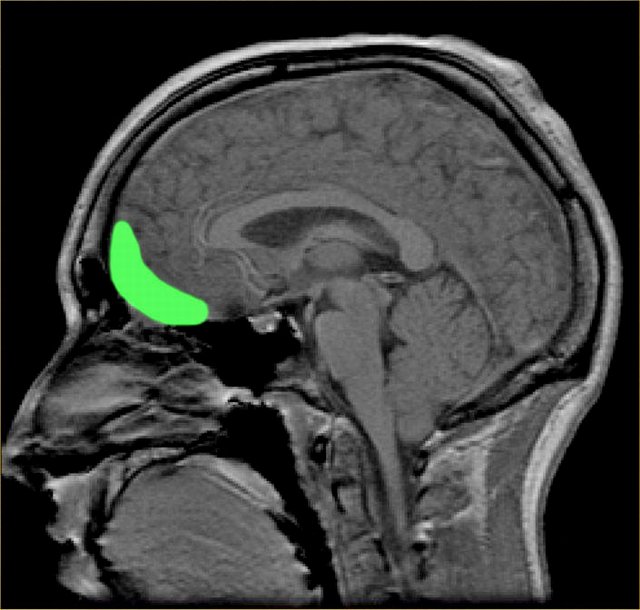

وتعتبر هذه الدراسة الأولى من نوعها (2013) حيث استخدم العلماء التصوير بالرنين المغنطيسي لأدمغة مجموعة من الشباب المدمنين على مشاهدة أفلام الجنس، إن نتائج الدراسة فاجأت العلماء بخطورة المناظر الجنسية، وضرورة الحد من مشاهدتها!!!

وتقول الدكتورة Dr Valerie Voon لقد وجدنا نشاطاً هائلاً في منطقة في الدماغ تدعى ventral striatum وهي المنطقة المسؤولة عن المكافأة والتحفيز والسعادة (المرجع رقم 1).

تظهر الصور الناتج عن المسح المغنطيسي أن المنطقة المسؤولة عن المكافأة في الدماغ تنشط بشكل غير عادي أثناء رؤية المشاهد الخلاعية، وإن تكرار هذه المشاهد يؤثر على الدماغ وينهكه تماماً بنفس تأثير المخدرات والخمر (المرجع رقم 3).